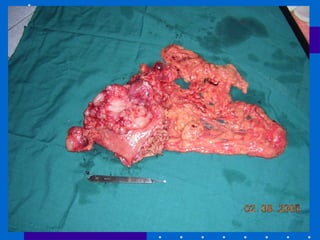

Surgical Interventions Gastrectomy total removal of the stomach result to no gastric juice for digestion, malnutrition,  pernicious anemia, weight loss Subtotal Gastrectomy removal of a part of the stomach and the remaining stomach is anastomosed  to the intestine Billroth I (Gastroduodenostomy ) – removal of the distal ½ of the stomach w/  anastomosis to the duodenum Billroth II (Gastrojejunostomy ) – removal of the lower stomach and antrium w/ anastomosis to the jejunum C . Vagotomy  – resection of the vagus nerve thus decreasing motility and gastric secretions

Gastric Cancer May develop in any part of the stomach but is found commonly at the distal third More common in men and in age 50-70 years old Causes :  heredity, chronic gastric ulcer, chronic gastritis S/Sx:  Gastric distress Flatulence Early satiety Loss of appetite, anorexia Loss of strength and weight loss Dx:  UGIS, absence of HCL – due to destruction of parietal cells by cancer cells Tx:  Gastrectomy, chemotherapy

Gastric Cancer